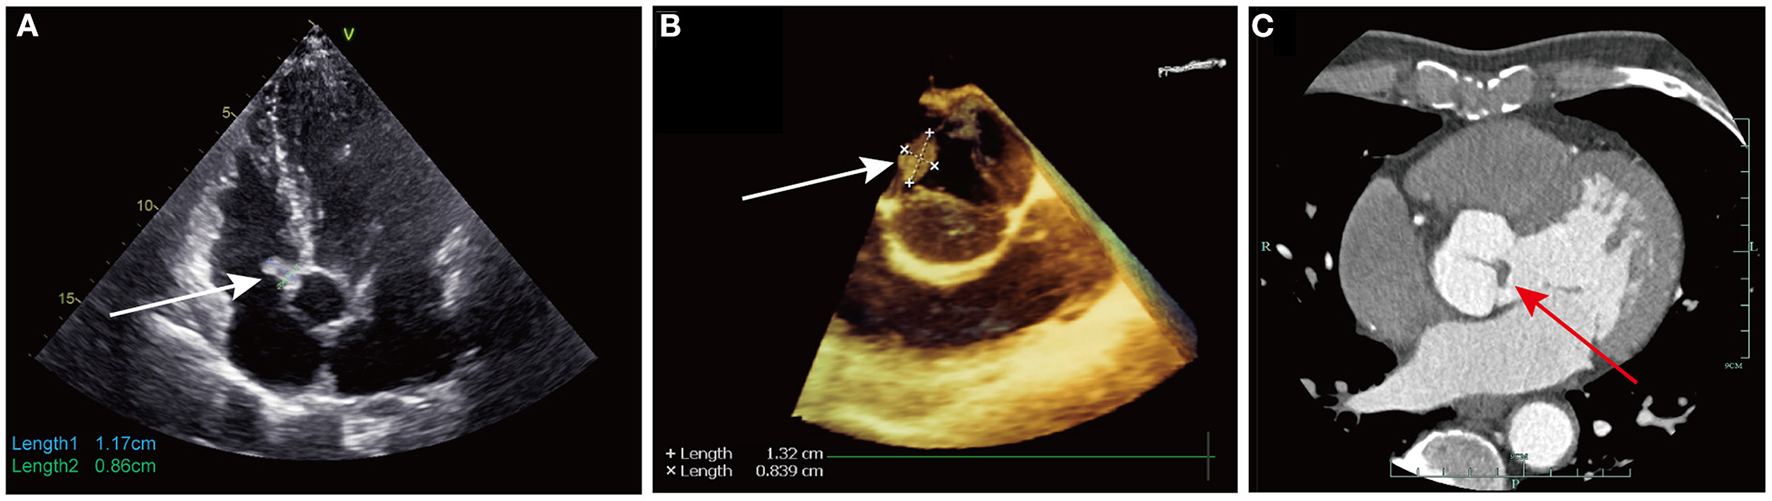

A 59-year-old Chinese male was admitted because of incidental findings of a right atrial mass on transthoracic echocardiography (TTE) during a routine check-up. No medical history has been reported to date. The laboratory results and physical examination findings were unremarkable. TTE revealed an irregular hyperechoic mobile mass (1.2 × 0.9 cm in size) with a stalk arising from the RA adjacent to the aortic root (Figure 1A). TTE also revealed thickened leaflets of AV, which was considered to be a degenerative change. No wall motion or other structural valve abnormalities were reported. Coronary computed tomography angiography (CTA) demonstrated no obvious stenosis of the coronary artery.

(A) Transthoracic echocardiography showed an irregular hyperechoic mobile mass (1.2 × 0.9 cm in size, white arrow) with a stalk arising from the right atrium adjacent to the aortic root; (B) Transesophageal echocardiography showed an additional mobile mass (1.3 × 0.8 cm in size, white arrow) on the ventricular side of the non-coronary cusp of aortic valve; (C) Coronary computed tomography angiography showed abnormal thickness of non-coronary cusp of aortic valve, which represented the cardiac papillary fibroelastoma (red arrow) on the aortic valve.

The patient was scheduled for minimally invasive excision of the right atrial mass via right anterolateral thoracotomy. Intraoperative transesophageal echocardiography (TEE) after anesthesia detected an additional mobile mass (1.3 × 0.8 cm in size) on the ventricular side of the non-coronary cusp of the AV (Figure 1B). Both right atrial and aortic valvular masses were considered CPFs due to their stippled edge and good mobility with stalks. Considering the high probability of AV preservation in cases of primary surgical indication for CPF based on our experience, we proceeded with the surgery via right anterolateral thoracotomy, without conversion to media sternotomy. Cardiopulmonary bypass was established through the femoral artery and vein cannulation. A 5 cm right mini-thoracotomy incision was made in the fourth interspace, which started medially to the anterior axillary line. Cardioplegia was achieved by antegrade perfusion of cold blood cardioplegia solution through a Y-shaped cannula. After transverse aortotomy, the tumor was located on the ventricular side of the noncoronary cusp of the AV (Figure 2A) and was easily excised by shaving its stalk. AV leaflet inspection confirmed their anatomical preservation. The aorta was then closed, and the heart resumed beating automatically. Then the tip of the cannula in the inferior vena cava was laid in the right atrium, 1 cm above the inferior atriocaval junction. No caval veins were snared and after transverse right atriotomy, a vacuum-assisted venous drainage controller was used to maintained the negative pressure ranging from−20 to−30 mmHg, or according to the blood level in the right atrium. The right atrial tumor (Figure 2B) was successfully excised on a beating heart by shaving its stalk (Supplementary Video 1). TEE revealed trivial AV regurgitation and complete excision of the masses. As only still echo images were regular archived, we retrospectively found abnormal thickness of non-coronary cusp of AV on coronary CTA, representing the CPF which was misdiagnosed as degenerative thickening of leaflet (Figure 1C). The postoperative course was uneventful and the patient was discharged on postoperative day six. After a 2-year follow-up, TTE showed no signs of CPF recurrence.